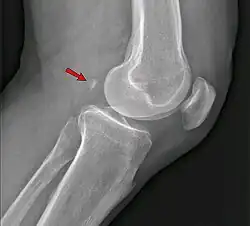

Fabela, no contexto da medicina, é um osso sesamoide situado na cabeça lateral do músculo gastrocnêmio nos membros inferiores, logo atrás da articulação do joelho.[1]

A sua função ainda é um mistério para a ciência. Já sua importância se deve, principalmente, por este ser bastante confundido com um fragmento ósseo ou um corpo estranho em radiografias da área. Segundo o pesquisador Michael Berthaume, do departamento de bioengenharia do Imperial College de Londres, "a fabela pode se comportar como outros ossos sesamoides, ajudando a reduzir o atrito nos tendões e redirecionando as forças dos músculos ou, como no caso da rótula, aumentando a força mecânica do músculo".[2]

A fabela localiza-se no tendão da cabeça lateral do músculo gastrocnêmio e aparece circundada em seu aspecto anterior e posterior pelas fibras tendíneas nos estudos histológicos. Está ligado na maioria dos casos à cabeça da fíbula por um ligamento fabelo-fibular. Seu tamanho é variável, entre 4 e 13 mm.